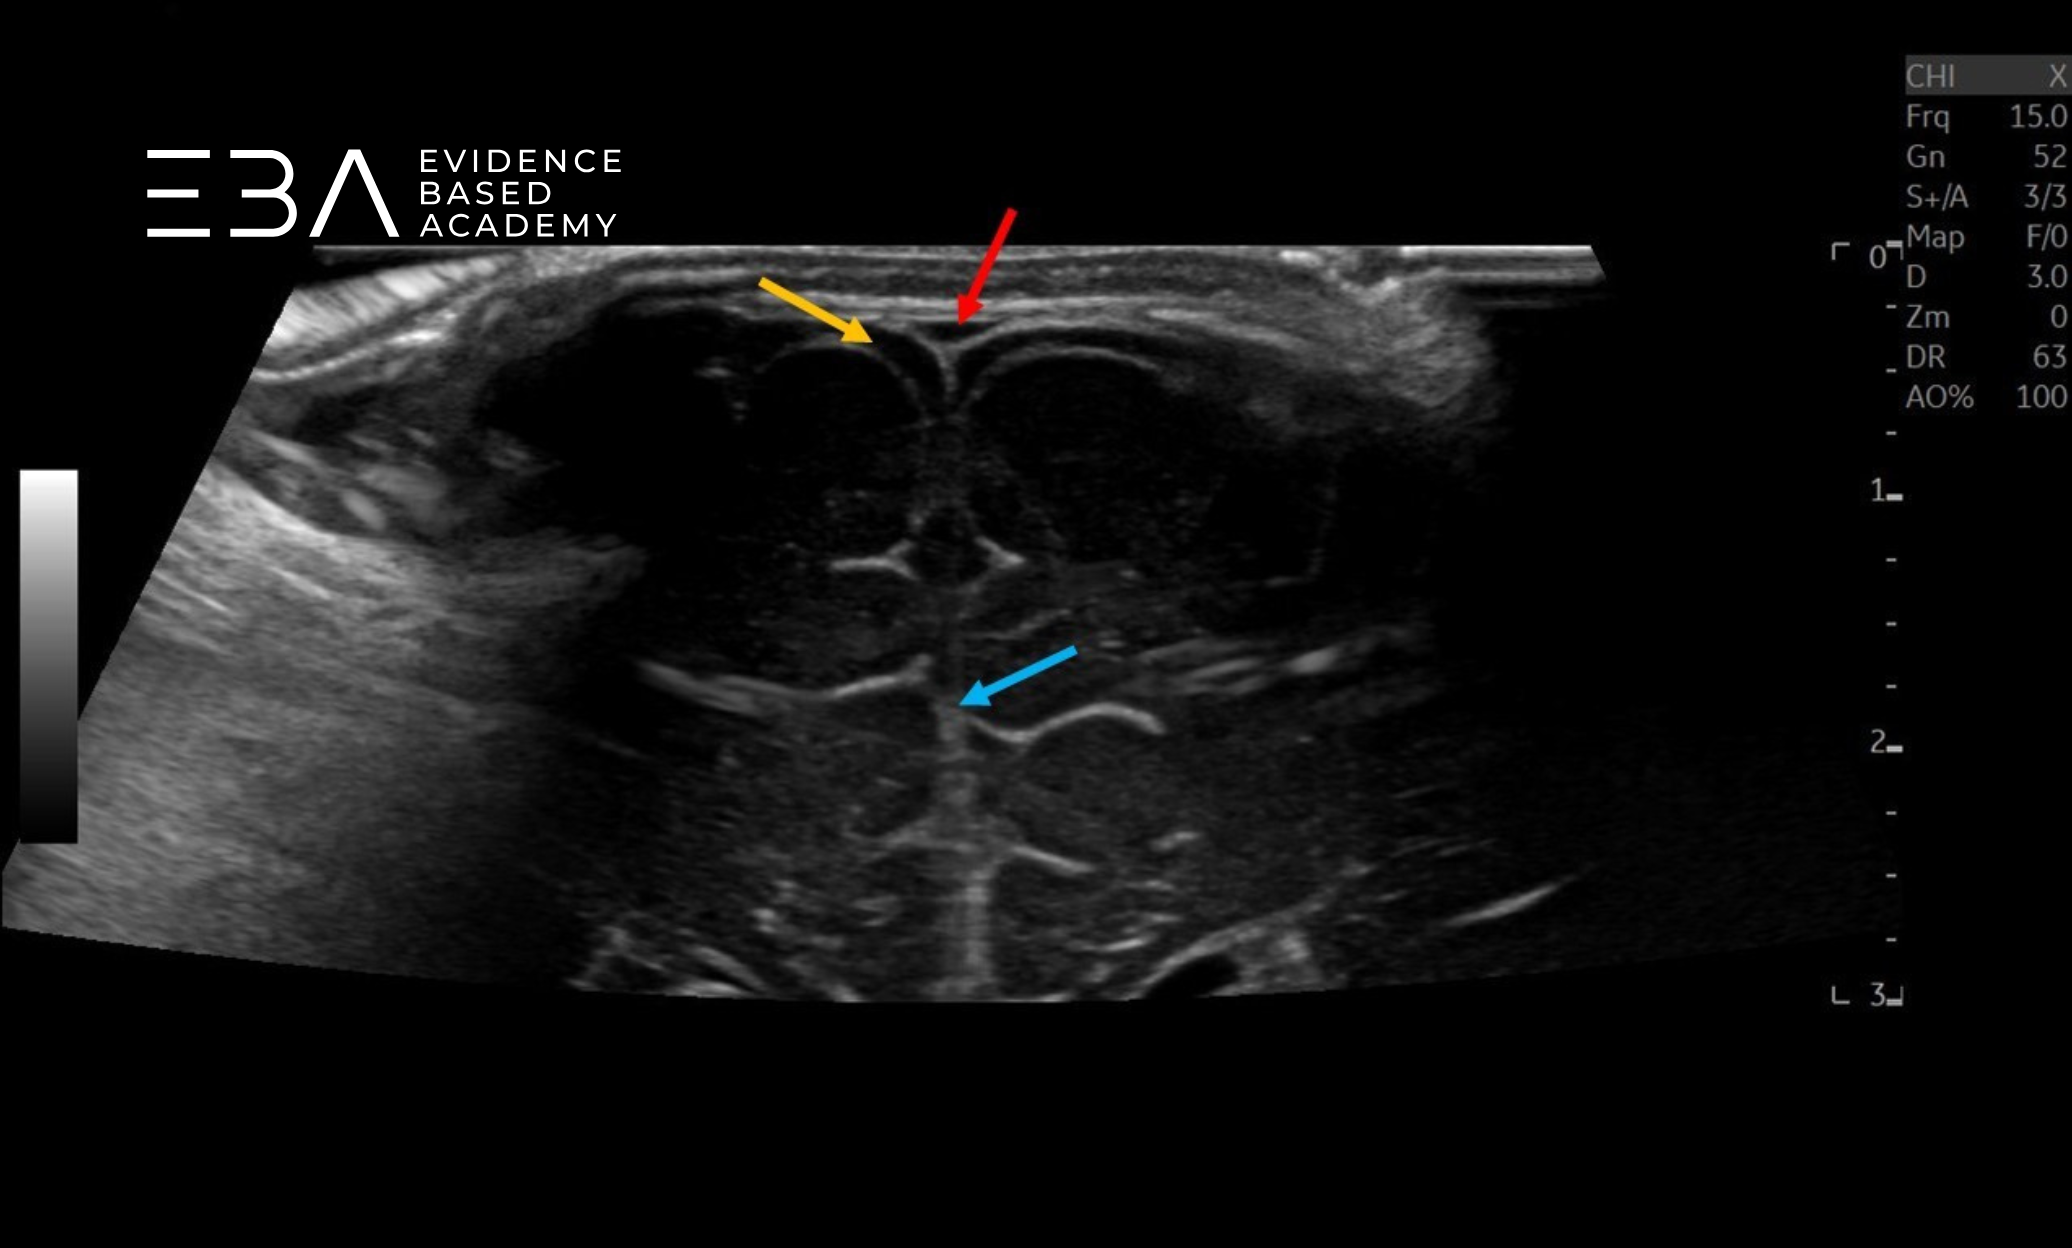

Badanie przez ciemiączko sutkowe

Obrazowanie przez ciemiączko sutkowe pozwala ocenić blaszki móżdżku, zbiornik wielki i komorę czwartą pod kątem prawidłowego wyglądu i wymiarów (6). Widoczne są również niektóre struktury nadnamiotowe, w tym tylna część układu komorowego, niekiedy komora trzecia, a także wzgórze, konary mózgu i zbiorniki podstawy mózgu (2). U wcześniaków przez to okno możemy dobrze uwidocznić również przeciwległą półkulę móżdżku (3).

zdj. 22

Głowica liniowa – badanie przez ciemiączko tylno-boczne. Półkula móżdżku (żółta strzałka), komora czwarta (czerwona strzałka).